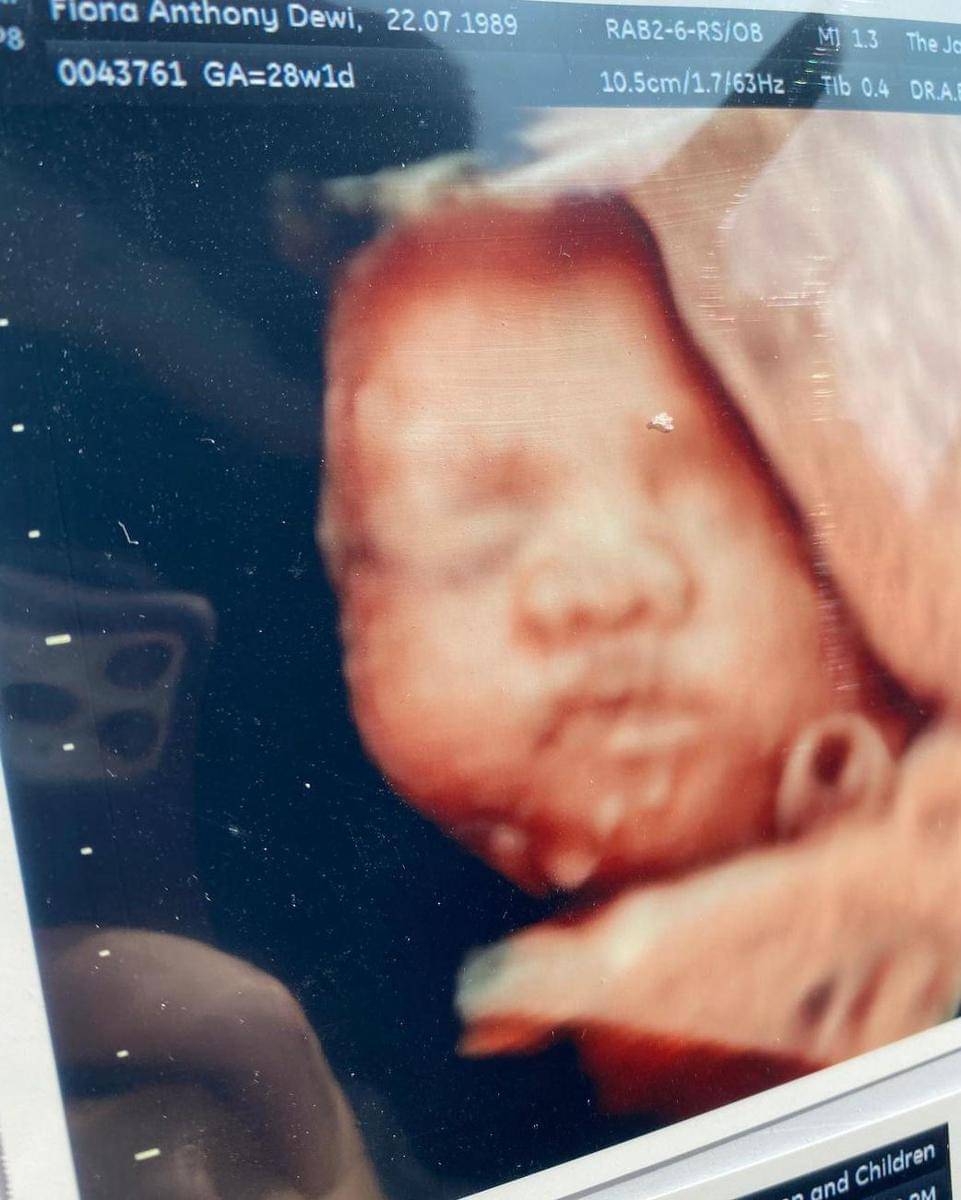

1. Melakukan cek USG

Selain membagikan foto dirinya yang sedang beraktivitas di usia hamil tuanya, Fiona juga membagikan foto perkembangan janin di kandungannya dalam bentuk foto hasil USG.

Melalui unggahan Instagram pada Senin (31/05/2021), Fiona membagikan foto buah hati yang telah menginjak usia 28 minggu. Berkat terknologi yang semakin berkembang, Fiona dan sang Suami dapat melihat secara jelas gambaran perkembangan wajah bayi dalam kandungannya.

"Fotonya udah jelas banget, serasa udah gede aja kamu nak. Sekarang jadi paham gimana excitednya tiap parents to be setiap kontrol rutin. Really can't wait to see your face every now and then!" tulis Fiona dalam unggahan hasil USG anak pertamanya itu.